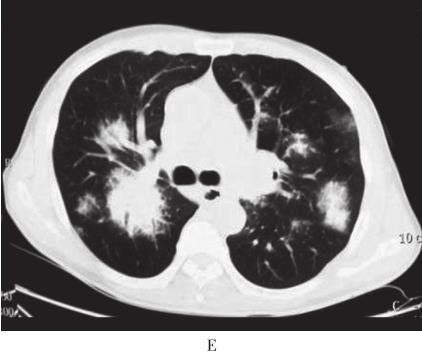

图1 胸部CT

A、B:2007年4月胸部CT示双肺野内多个大小不等团片状高密度.C、D:2009年10月胸部CT示双肺多发结节样、团块样病.E~G:2010年10月胸部CT示右肺下叶巨大团块状类软组织密度影,双肺弥漫性团片状浸润及实变影,纵隔内多发肿大淋巴结;胸片示右下肺团块影,双肺多发结节影

入院后体格检查:一般情况佳,双侧颈部、锁骨上、腋窝、腹股沟可触及数枚肿大淋巴结,最大直径约2cm,质硬,边界清,活动度可,无压痛。双肺呼吸音粗,可闻及广泛哮鸣音。心、腹检查未见异常,肝脾肋下未触及。入院时实验室检查:血常规:WBC 5×109/L,HGB 111g/L,PLT 368×109/L;外周血涂片:白细胞正常范围,淋巴样浆细胞约占5%,成熟红细胞呈明显缗钱样排列,血小板增多。凝血功能检查:PT 15.2秒,凝血酶原活动度74%,APTT 43.9秒;血清肿瘤标志物及自身抗体谱检查阴性;PPD试验阴性;多次痰病原学检查阴性;C反应蛋白CRP)10.8mg/L;ESR 105mm/h;血β2微球蛋白44.9ng/L;血清总蛋白106g/L,血清白蛋白35g/L,白蛋白/球蛋白0.49。胸部X线示:右下肺团块影,双肺多发结节影。胸部CT示:右肺下叶巨大团块状类软组织密度影,双肺弥漫性团片状浸润及实变影、纵隔内多发肿大淋巴结图1E和F)。支气管镜:右上叶、右中叶、右下叶、左上叶、左下叶背段支气管开口黏膜充血水肿,可见不规则隆起,向腔内生长,触之易出血,表面光滑;右下叶、左上叶支气管开口完全闭塞;于右下叶开口行支气管黏膜活检。该患者有乏力、鼻黏膜出血倾向等高黏滞血症表现,血清总蛋白106g/L,血清白蛋白35g/L,提示患者存在血清球蛋白异常增多。遂继续查免疫球蛋白定量、血清蛋白电泳及骨髓穿刺活检。结果为:IgM 87.30g/L、IgA 0.73g/L、IgG 8.14g/L、κ轻链100g/L、λ轻链3.49g/L;血清蛋白电泳及免疫固定电泳显示M成分为IgM κ,尿本周蛋白阴性。骨髓形态学示:红系增生,分类以中晚幼红为主,可见巨变、类巨变、双核红,成熟红细胞呈明显缗钱样排列;淋巴样浆细胞多见,约占23%;骨髓瘤细胞约占6%。血清单克隆IgM升高,血清免疫固定电泳检出IgM κ,外周血及骨髓中淋巴样浆细胞增多,支气管黏膜、骨髓及淋巴结活检组织标本病理均提示淋巴细胞浸润,表达CD20、CD79α、CD138等B细胞免疫表型,且轻链呈限制性表达(表1)。支气管黏膜活检示均匀一致的小淋巴细胞弥漫浸润,结合免疫组化结果,符合黏膜相关淋巴组织结外边缘区B细胞淋巴瘤(MALToma)。患者既存在骨髓侵犯,又存在单克隆性IgM分泌,故诊断为华氏巨球蛋白血症(Waldenström macroglobulinemia,WM),肺部多发占位为华氏巨球蛋白血症肺部浸润,伴局部肺不张。

WM本病是一种兼具B淋巴细胞、浆细胞特点的低度恶性淋巴瘤。多起病缓慢,病初可无症状,临床表现多种多样,常不典型,容易误诊。本例患者以呼吸系统症状为首发表现,经病理证实为WM肺浸润,临床上十分少见。本病例的肺部影像学特点为胸部CT示双肺多发结节状、团块状病灶及实变影、纵隔内多发肿大淋巴结,起初根据影像学特点被误诊为肺癌或肺部感染,后因经验性抗感染治疗疗效不佳及病情迁延,继而被误诊为慢性肺部炎症性疾病,如肉芽肿病等。因此,对于临床表现和胸部影像学检查缺乏特异性的患者,在常见疾病不能完全解释病情或抗感染治疗无效的情况下,要考虑肺部少见疾病或全身性疾病的肺部表现的可能。该患者支气管黏膜标本轻链免疫组化结果与淋巴结、骨髓免疫组化结果差别较大,请病理科复核后,考虑可能与支气管黏膜取材组织少、染色欠佳、不稳定及肿瘤细胞异质性等有关。此时应结合血清免疫固定电泳及骨髓、淋巴结等大标本的结果进行综合分析。